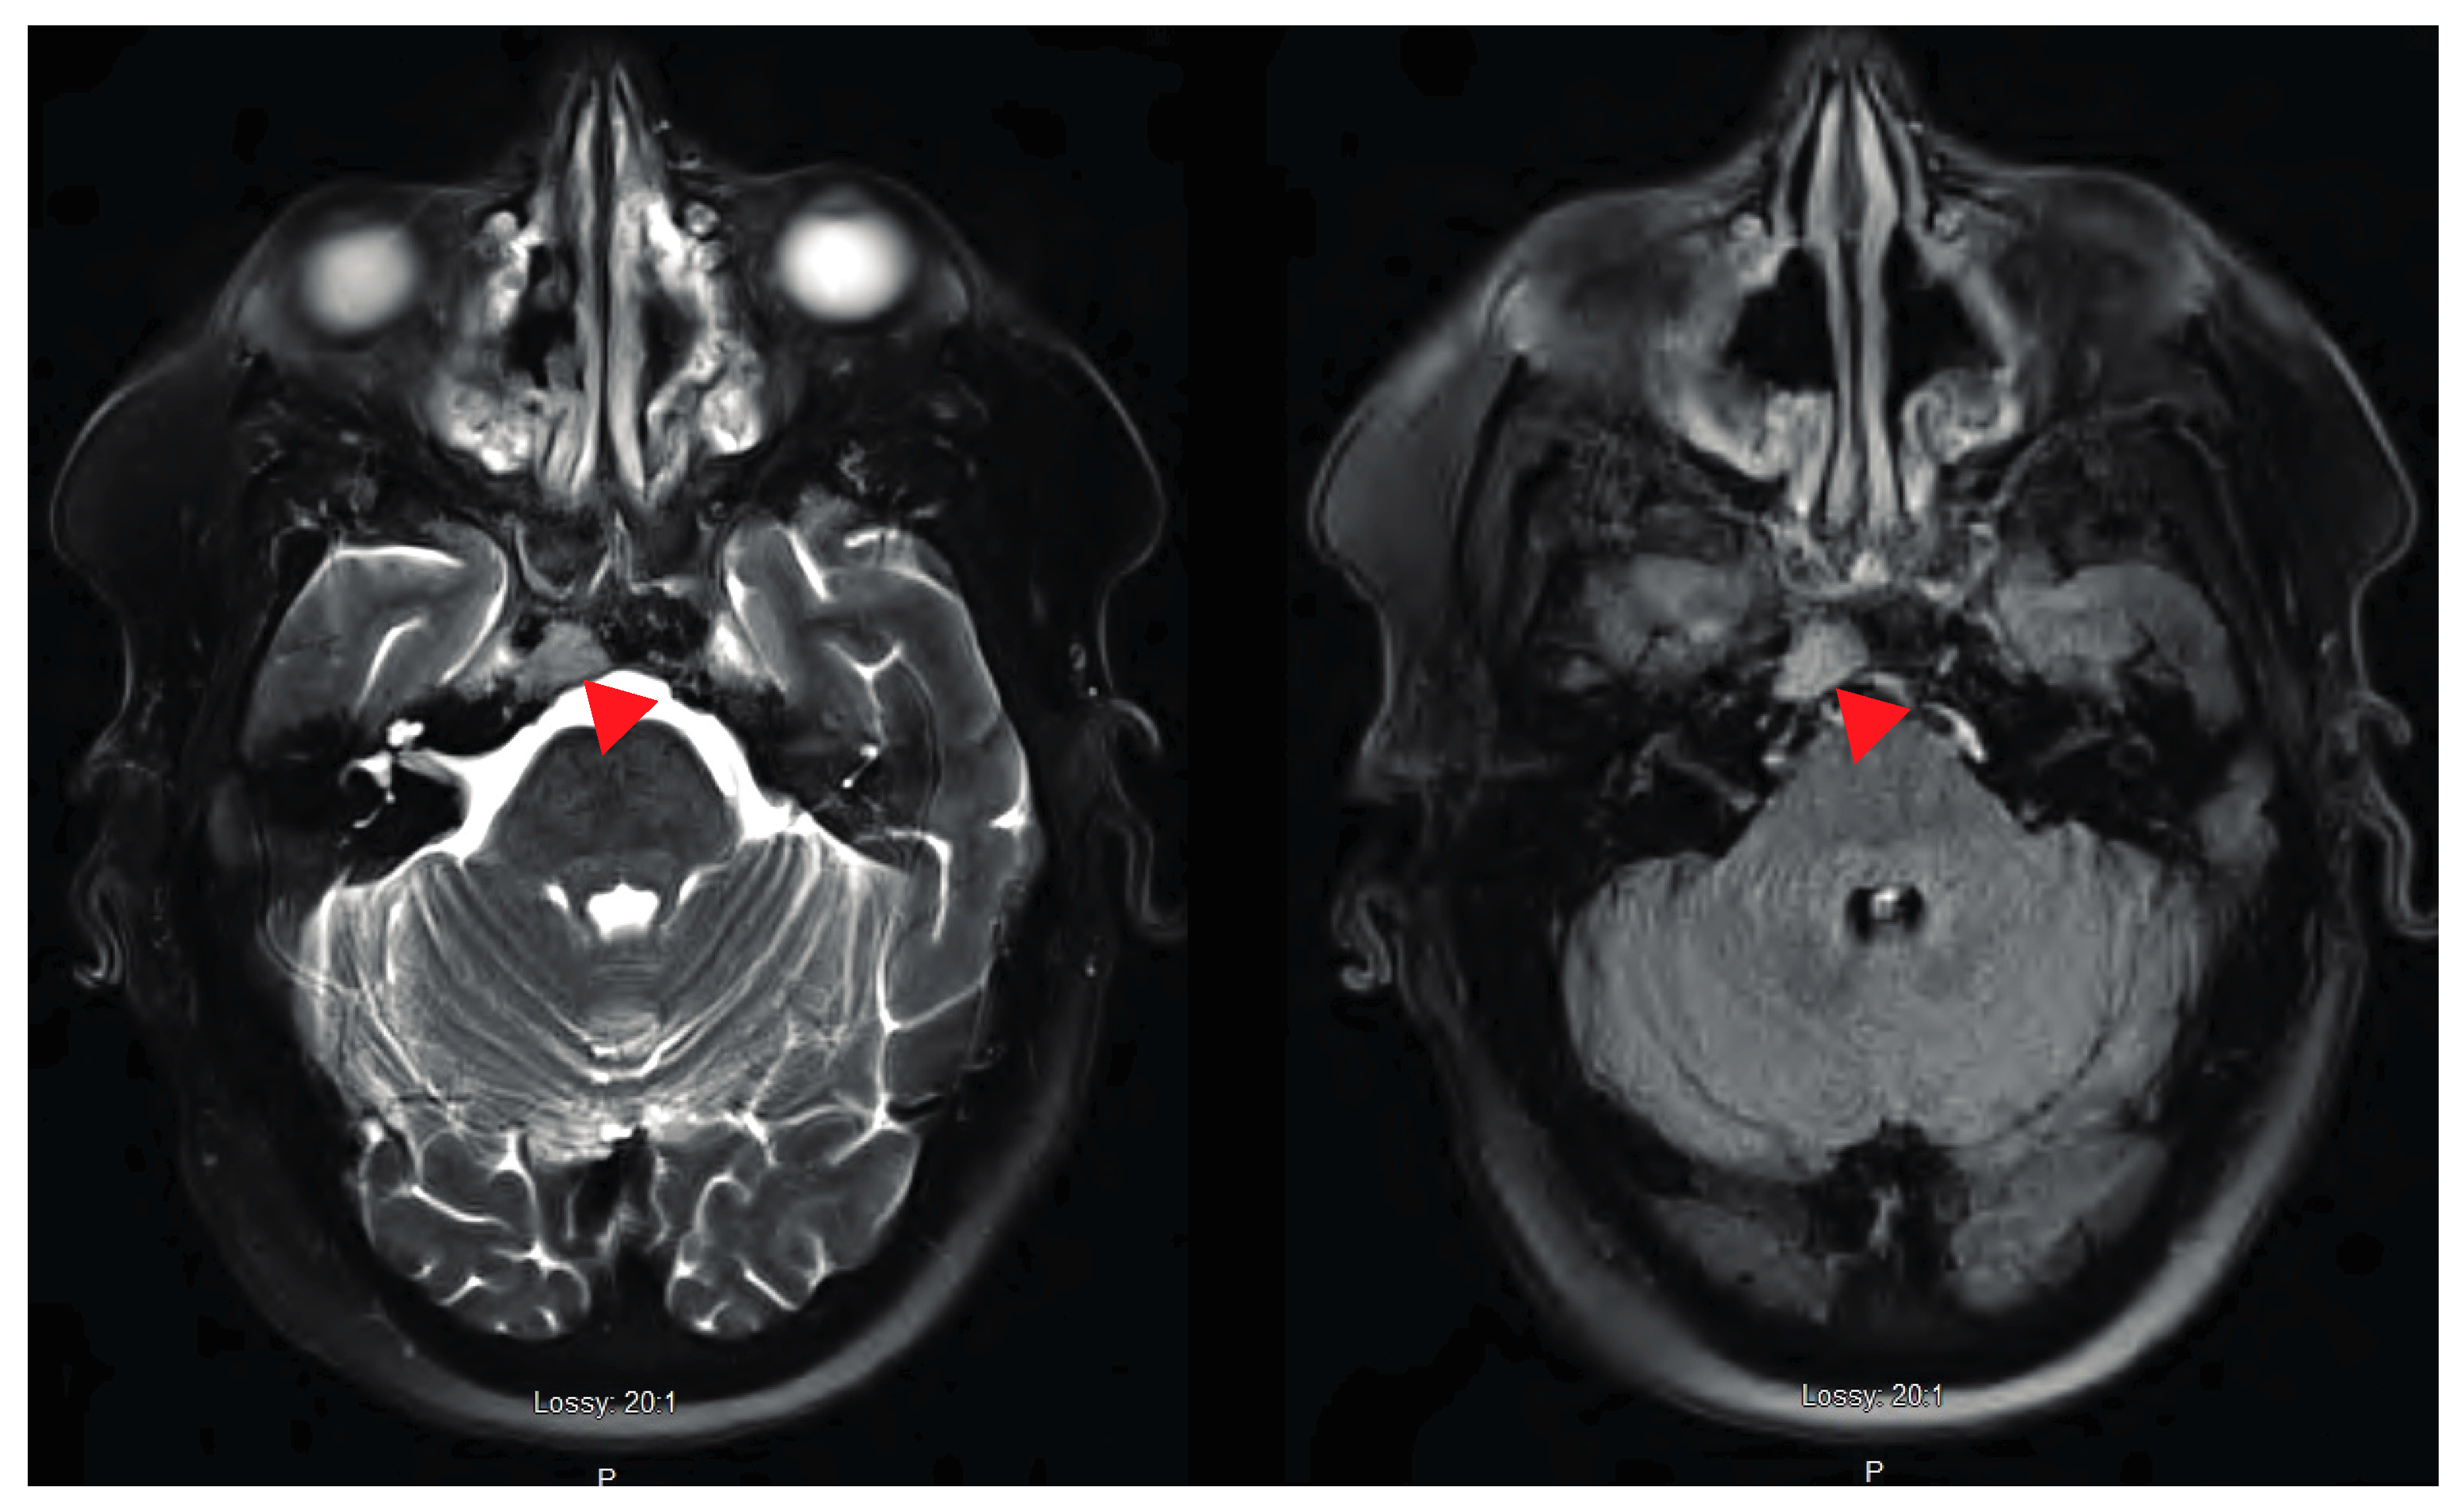

2. Case Presentation